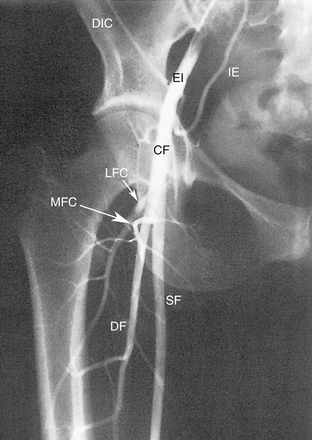

Артериальное дерево нижних конечностей начинается от бифуркации аорты, и эта часть сосудистой сети включена в эту главу. Подробную информацию об анатомии сосудов брюшной полости см. в главе 26 . Основные артерии нижних конечностей графически показаны на рисунке 13-8 . Рисунки с 13-9 по 13-13 представляют собой ангиографические изображения региональной артериальной анатомии нижней конечности.

РИСУНОК 13-9. А. Брюшная аорта (Ао) заканчивается разветвлением на общие подвздошные артерии (CI) на уровне позвонка L4. Б. Общие подвздошные артерии делятся в пояснично-крестцовом соединении на внутреннюю (II) и наружную подвздошную (EI) артерии. Внутренняя подвздошная артерия (также называемая подчревной артерией) снабжает внутренние органы и мускулатуру таза. Ветви этой артерии становятся важными сопутствующими путями, как видно на других рисунках. Наружная подвздошная артерия переходит в общую бедренную артерию у паховой связки, как показано на рисунке 13-10 . C : Трехмерная объемная (VR) компьютерная томографическая (КТ) ангиограмма аорты и сегмента подвздошно-бедренной артерии. D. Проекция максимальной интенсивности (MIP) КТ-ангиограммы подвздошно-бедренных сегментов демонстрирует очаговые кальцификации в открытых сосудах. E — магнитно-резонансная ангиограмма (МРА) с усилением гадолинием аорты, подвздошного и бедренного сегментов. Анатомия наглядно иллюстрируется методами трехмерной реконструкции. С, чревная артерия; H, печеночная артерия; НМА, нижняя брыжеечная артерия; R, левая почечная артерия; рРГ – замена правой печеночной артерии; S, селезеночная артерия; СМА, верхняя брыжеечная артерия.